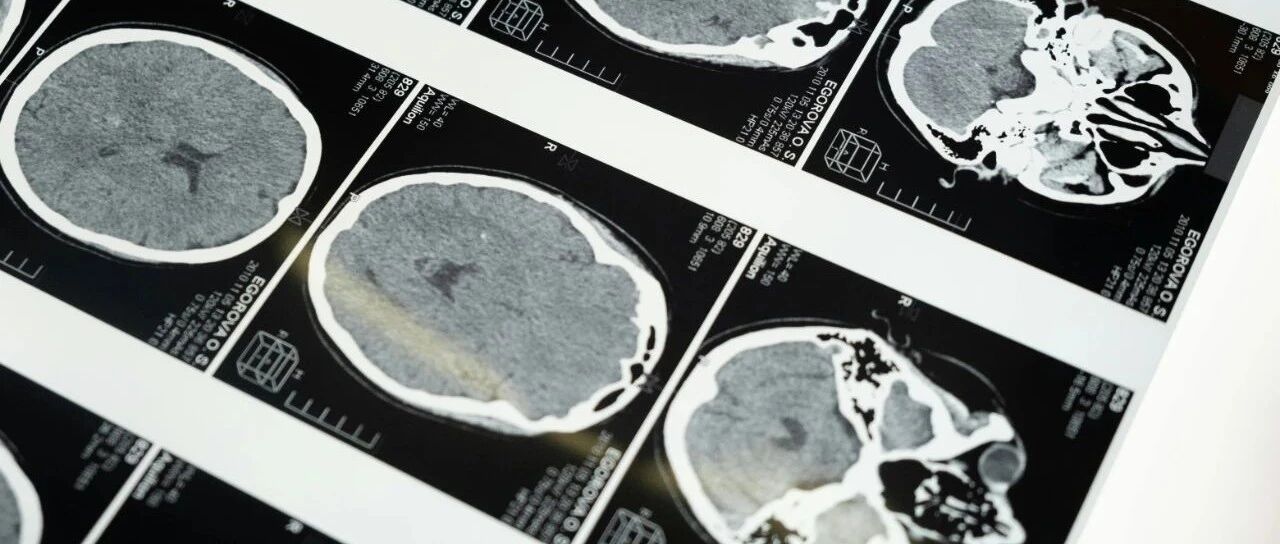

Doctors revealed that the hemorrhage occurred in the left motor cortex of her brain, an area closely associated with language processing. While the woman had studied abroad for over a year and was previously fluent in English, the bleeding specifically disrupted the neural pathways responsible for her second-language function.

Medical experts explained that brain functions, especially those related to language, are highly localized. In her case, the damage impacted her ability to access English vocabulary, even though her native languages remained unaffected.